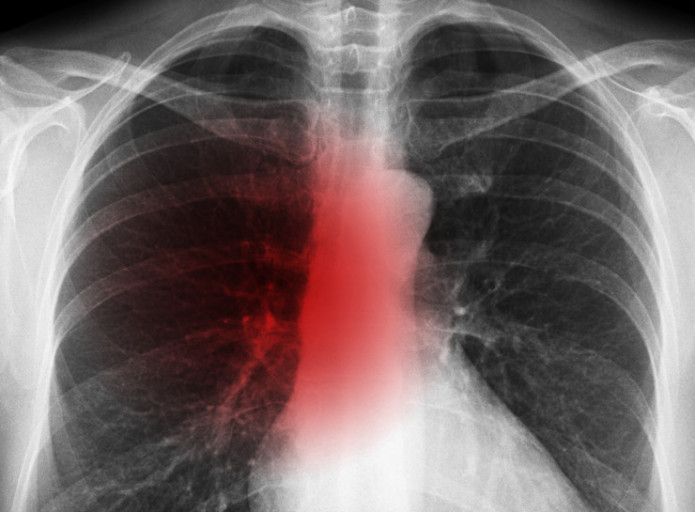

오늘은 단순한 감기와는 달리, 폐에 염증이 생기는 심각한 질환인 폐렴의 증상에 대해 이야기하려 합니다. 폐렴은 세균, 바이러스, 곰팡이 등 다양한 원인에 의해 발생하며, 특히 면역력이 약한 어린이나 노인에게 치명적일 수 있습니다.

폐렴은 보통 갑작스럽게 시작되며, 호흡기 증상과 함께 전신 증상이 복합적으로 나타납니다. 다음은 폐렴 환자들이 흔히 겪는 10가지 주요 증상입니다.

- 호흡 곤란 및 가슴 통증

- 설명: 폐렴의 가장 심각하고 중요한 증상입니다. 폐에 염증이 생겨 폐 기능이 떨어지면서 숨쉬기 힘들어지며, 얕고 빠른 호흡을 하게 됩니다. 심한 경우 가슴에 통증을 느끼거나, 옆구리가 결리는 듯한 느낌을 받을 수 있습니다.